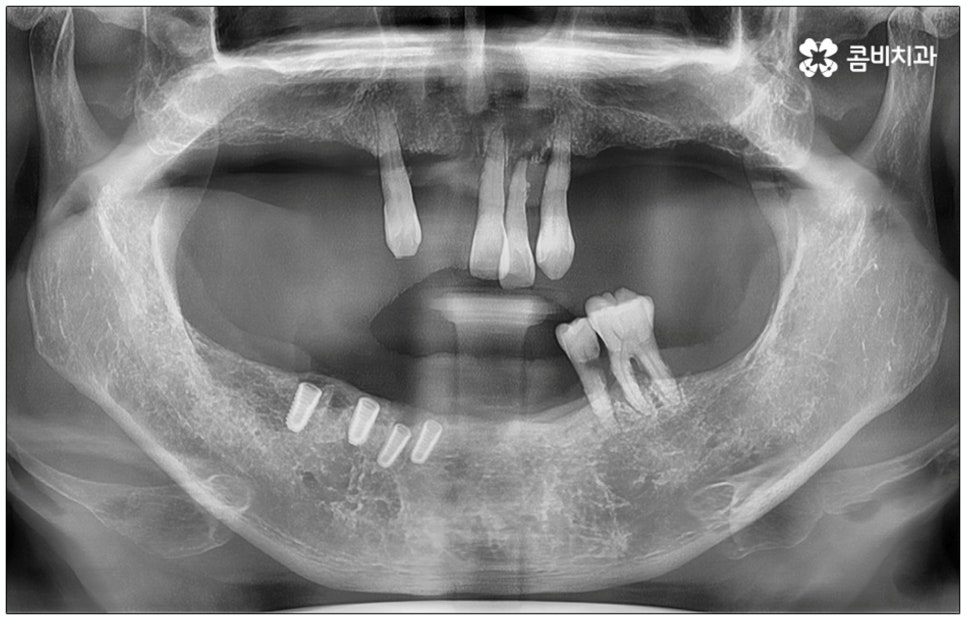

전신 질환을 앓고 있는 분들이나 고령의 환자분들, 다수의 임플란트가 필요한 분들의 경우 컴퓨터 분석을 활용한 임플란트 방식을 통해 도움받아 볼 수 있는데요. 네비게이션 임플란트라고 불리는 이 방식은 첨단 장비를 통해 육안으로 확인하기 어려운 구강 내부의 골조직, 신경 등의 해부학적 구조를 살펴본 다음 3D 모의 수술을 통해 최적의 수술 경로를 찾아내어 가이드를 제작하고 이를 장착하여 그대로 진행하기 때문에 보다 정확하고 안전하게 노인임플란트 수술을 진행할 수 있습니다.

이러한 네비게이션 임플란트 방식은 디지털 기술로 위험 요소를 사전 분석하여 식립 위치와 각도를 보다 정교하게 예측하기 때문에 임플란트 부작용의 발생률을 낮추고 식립 안정성을 높일 수 있는데요. 무절개 또는 최소절개 수술이기 때문에 시술 시간이 짧고 통증이 적으며 회복 기간이 빠르다는 장점을 가지고 있으나 정밀 검진 후 상황상 골유착 과정의 안정성이 떨어질 수 있는 케이스의 경우에는 절개 및 개방 후 수술을 진행하는 것이 좀 더 유리하기 때문에 꼼꼼한 검진, 정확한 판단, 의료진의 높은 숙련도가 굉장히 중요하다고 할 수 있어요.

특히 다수의 치아를 상실했을 때 전체적인 교합, 골조직 및 잇몸 상태, 얼굴형과의 조화 등 모든 부분을 종합적으로 고려하여야 하며 노인임플란트 수술의 경우 다양한 변수가 발생할 수 있기 때문에 이러한 고난도 임플란트 케이스에 노련하게 대처할 수 있도록 풍부한 임상 경험과 노하우를 갖춘 의료진인지, 정밀 검진 기계를 보유하고 있는지, 처음부터 끝까지 철저한 케어 시스템을 갖추고 사후 관리까지 꼼꼼하게 진행하는지 등을 잘 살펴보시고 임플란트 수술을 진행할 치과를 신중하게 선택하시길 권유드리고 있습니다.